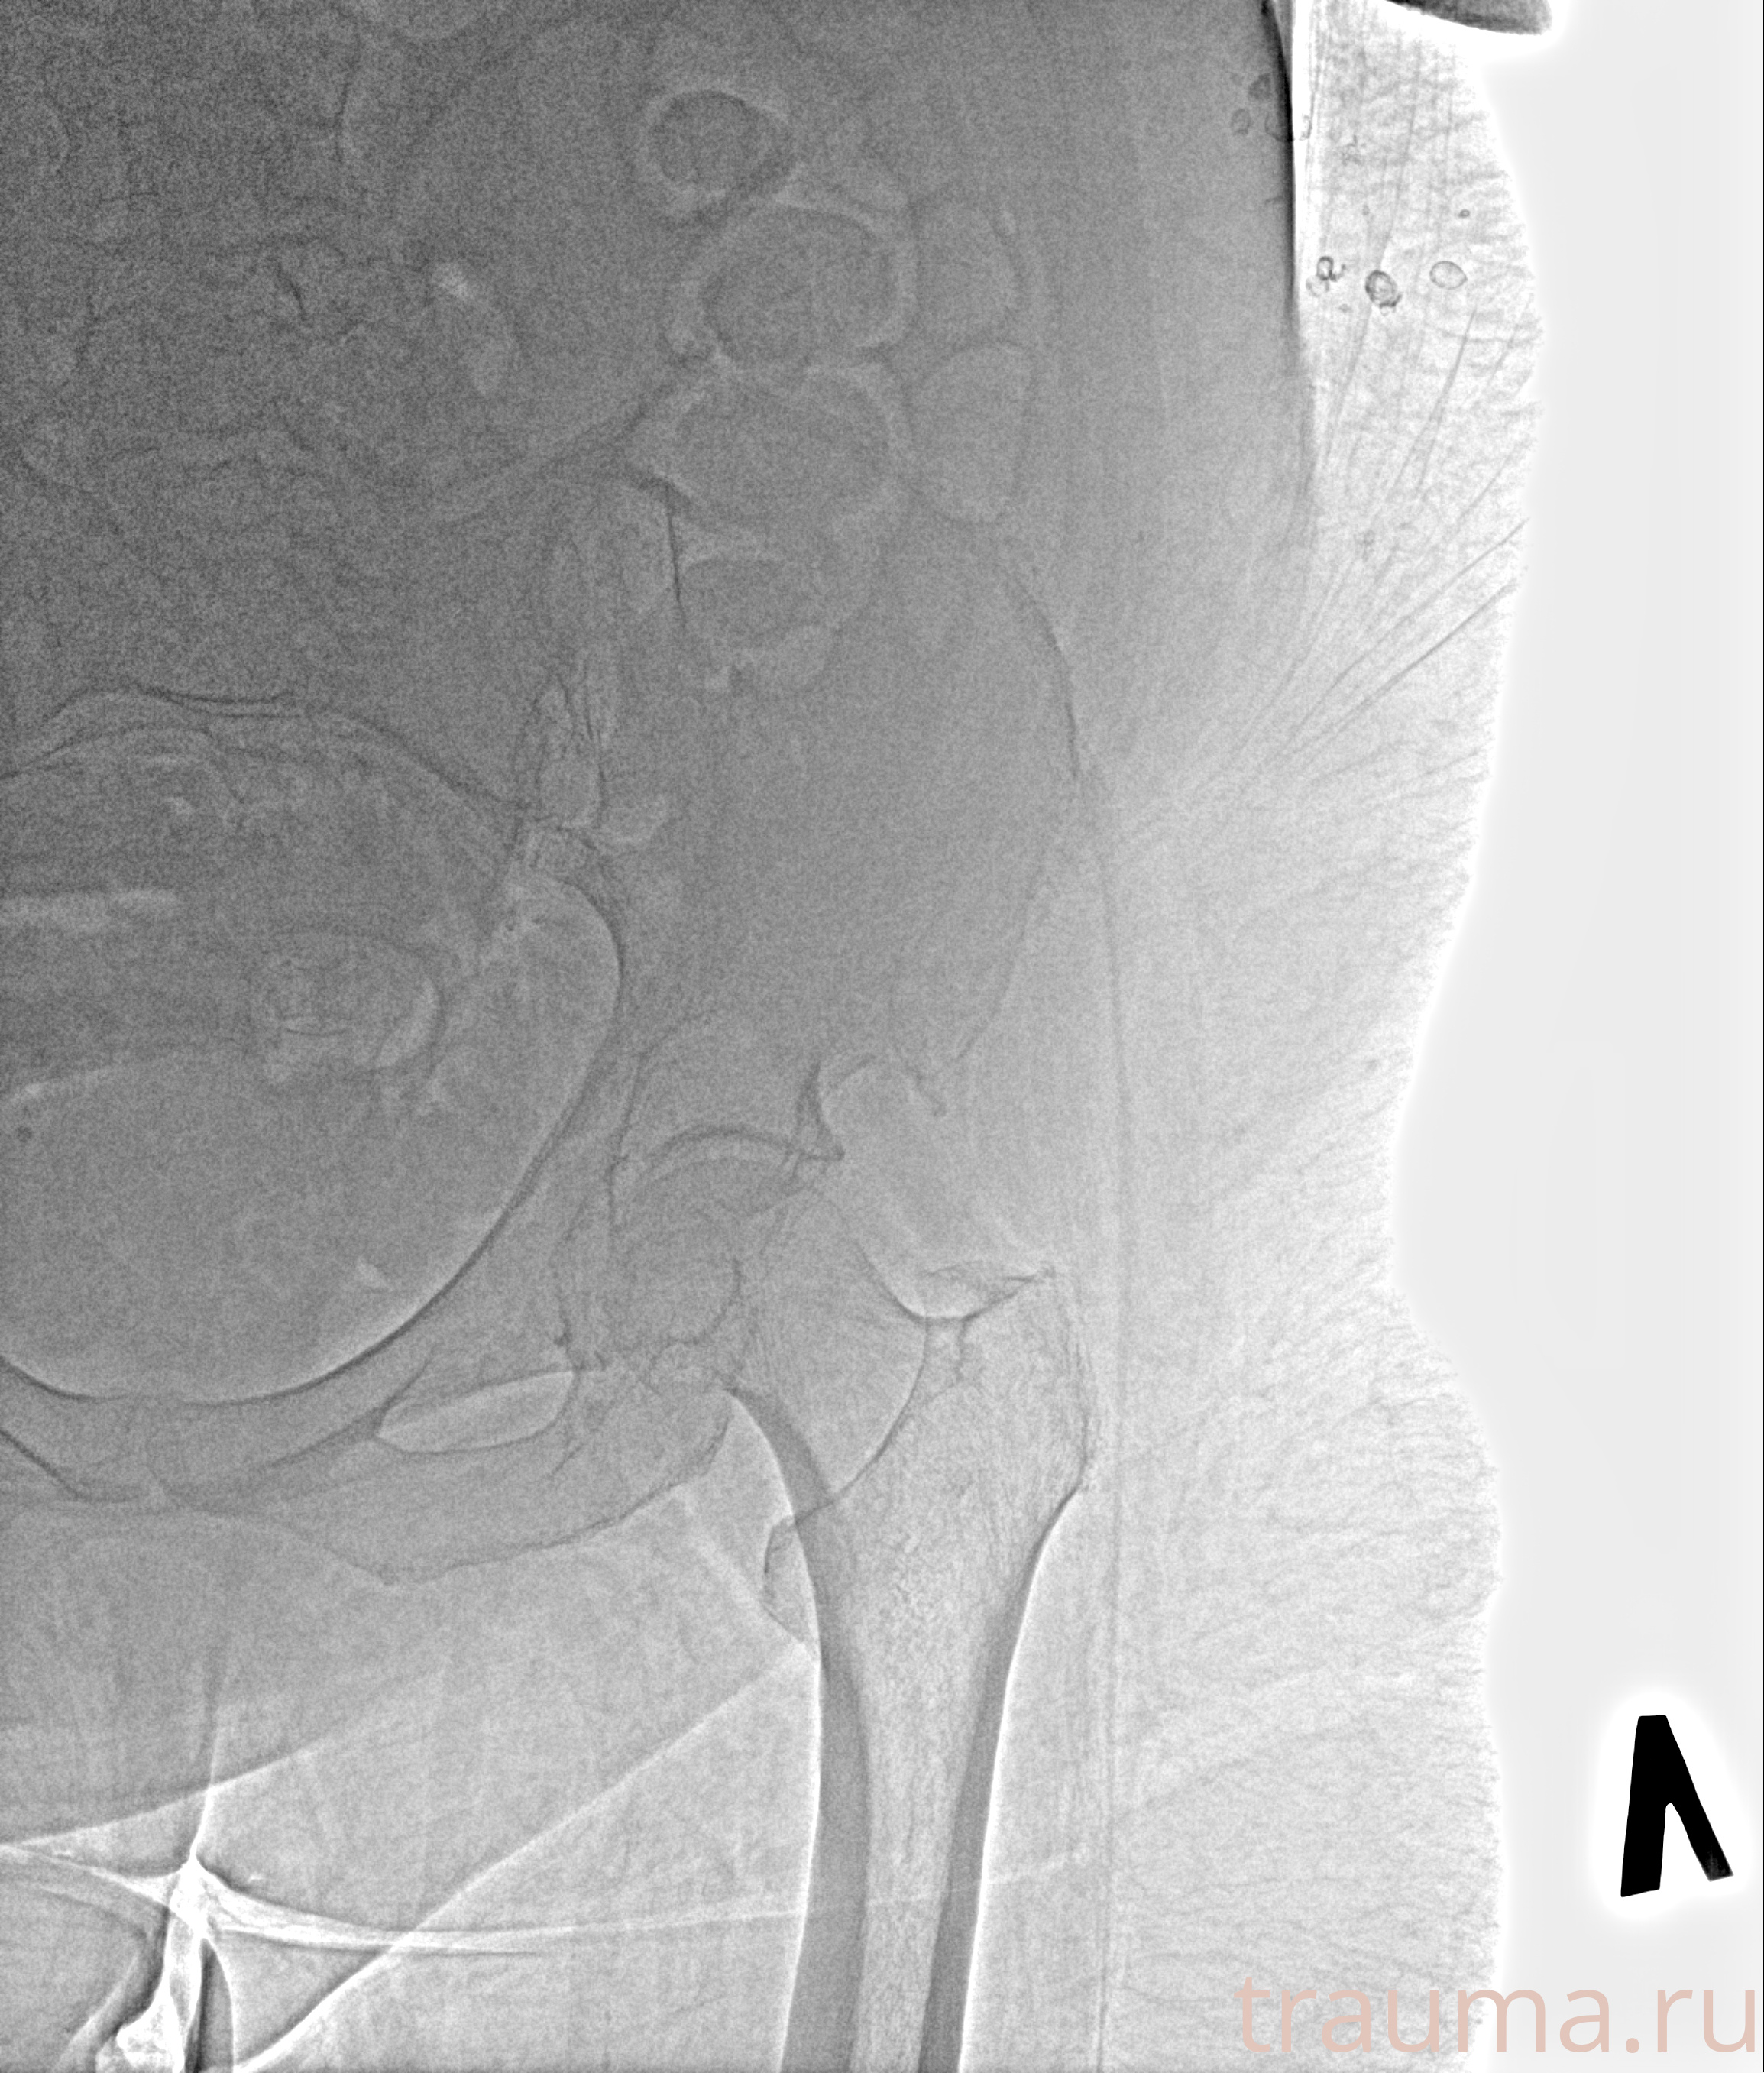

Рентген на дому: по вашему адресу приезжает врач-рентгенолог, травматолог-ортопед с мобильным рентгеновским аппаратом, проводит диагностику травмы или заболевания, делает необходимые рентгенограммы, дает рекомендации по дальнейшему лечению. Получить качественные снимки в домашних условиях возможно благодаря уникальной методике, разработанной МосРентген Центром для института  Склифосовского